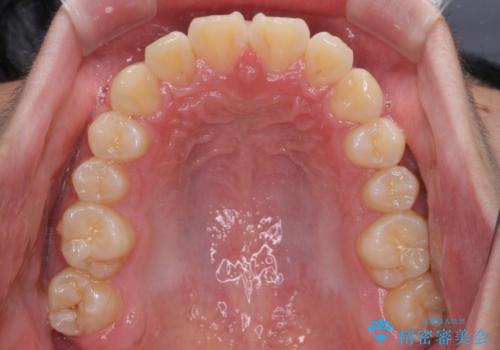

中学生と言うこともあり、1年強の短期間で終了しました。

歯磨きがしっかりとできないと虫歯になるリスクがありましたが、治療期間中は清潔な状態を保っていただけました。